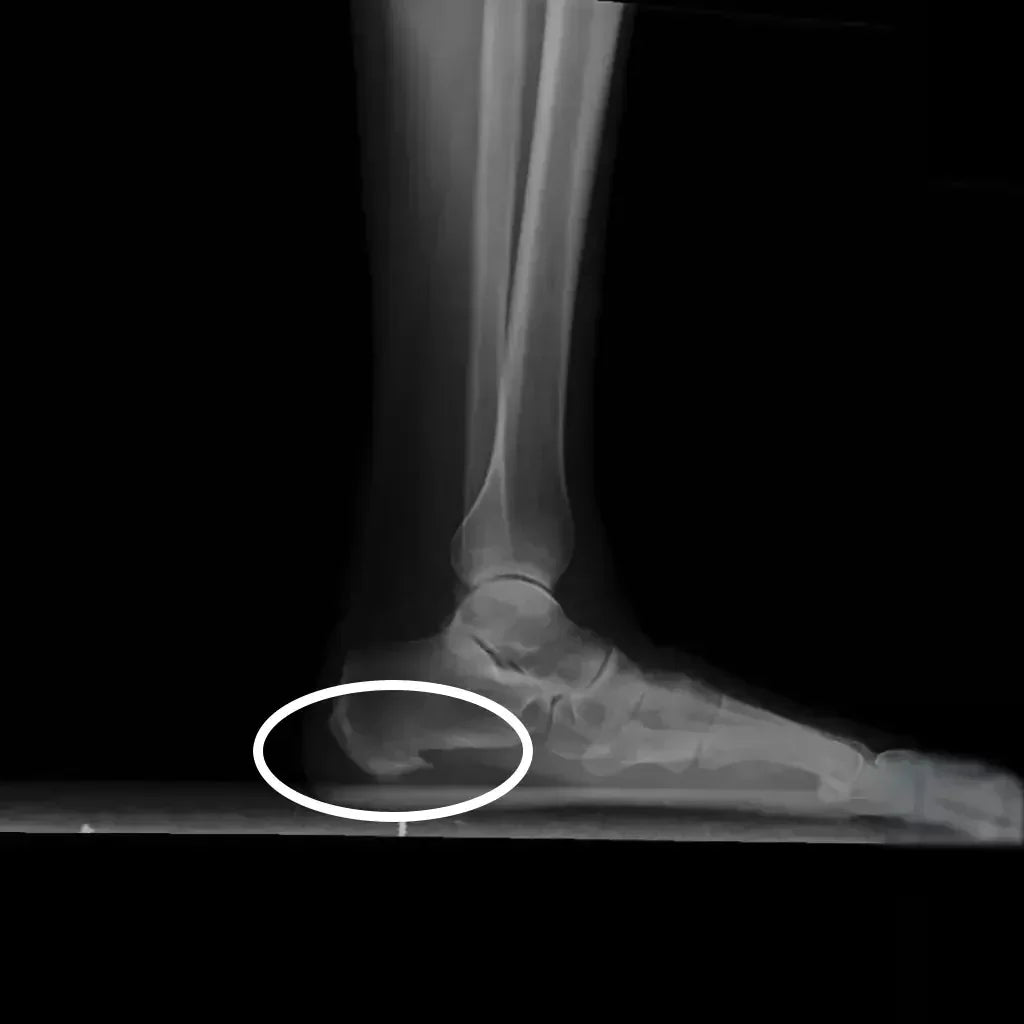

¿Qué es el espolón calcáneo?

El espolón calcáneo es una protuberancia ósea que se forma en el hueso del talón (calcáneo) debido a la acumulación de depósitos de calcio en la zona donde se inserta la fascia plantar. Esta afección puede provocar un dolor intenso y estar relacionada con la fascitis plantar, una inflamación de la fascia que recubre la planta del pie.